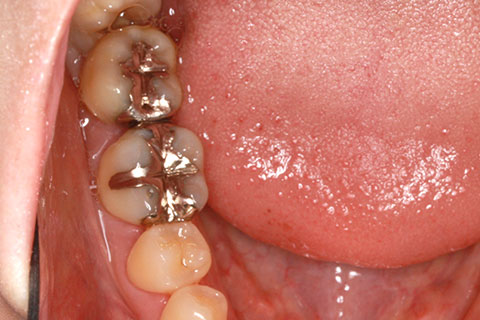

• ジルコニアブリッジの症例3

治療前

治療後

年齢・性別

25歳女性

治療期間

1ヶ月

抜歯

右下5番欠損

治療費

16.5万円(税込み)

備考

歯質の削除量を最小限に抑えるブリッジ治療

治療内容

欠損部位の隣接歯を削合後、セメント合着

施術の副作用(リスク)

知覚過敏、歯髄炎、荷重負担